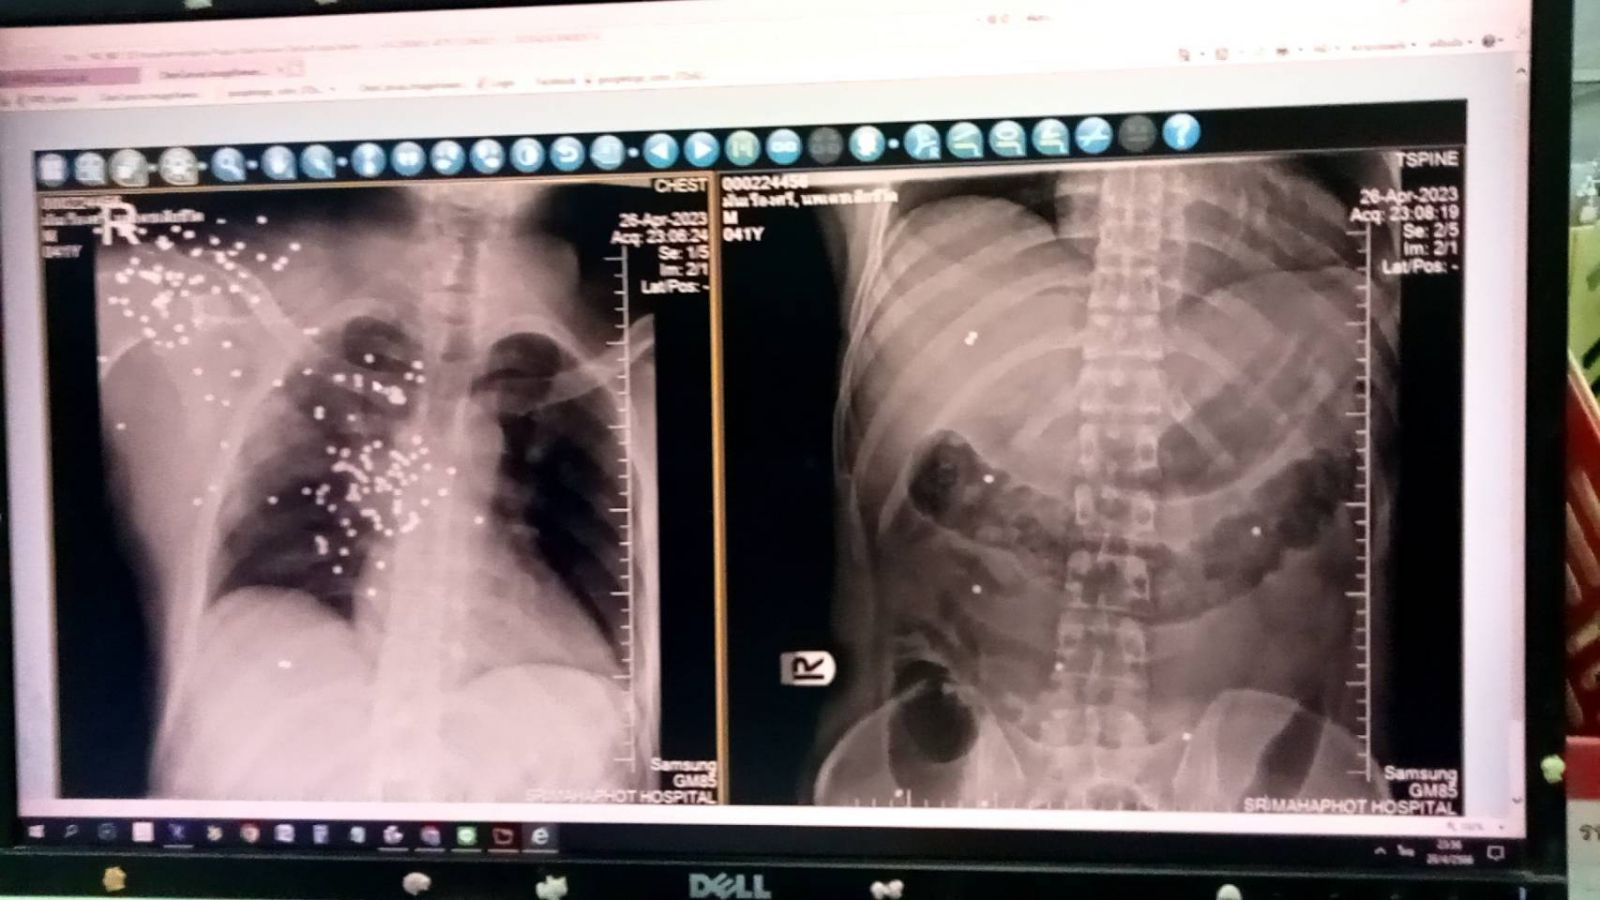

ทราบว่าผู้ได้รับบาดเจ็บเป็นชาย 1 ราย ถูกยิงด้วยอาวุธปืนลูกซองสั้นไทยประดิษฐ์ที่ราวนมขวา 1 แห่ง และก้นกบนอนจมกองเลือดบริเวณหน้าบ้านเลขที่58-236 และ ตรวจพบปลอกกระสุนปืนลูกซองสีเขียวตกอยู่บริเวณหน้าบ้าน 1 ปลอกและห่างจากหน้าบ้านที่เกิดเหตุ 50 เมตรพบกระสุนปืนลูกซองยาวอีก 1 ปลอก อาสาสมัครหน่วยกู้ภัยร่วมกตัญญูได้นำตัวส่งโรงพยาบาลศรีมหาโพธิ และ เสียชีวิตระหว่างทางขณะนำตัวส่งโรงพยาบาล ทราบชื่อผู้เสียชีวิตคือ นายนพเดช มั่นเรืองศรี อายุ 41 ปี อยู่บ้านเลขที่ 58/236 หมู่ที่ 3 ต.กรอกสมบูรณ์ อ.ศรีมหาโพธิ จ.ปราจีนบุรี